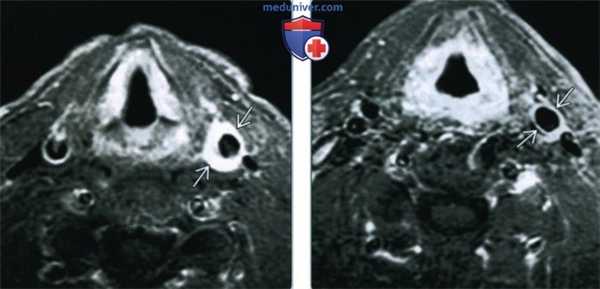

(Слева) МРТ Т1ВИ FS с КУ, аксиальный срез. Пациента беспокоит болезненность при пальпации области сонной артерии. Стенка общей сонной артерии утолщена, интенсивно накапливает контраст. Такие признаки характерны для каротидинии. Обратите внимание, что просвет сосуда не сужен.

(Справа) МРТ Т1ВИ FS с КУ, аксиальная проекция. Пациент с каротидинией после курса системных кортикостероидов. Отмечается небольшое остаточное утолщение стенки левой общей сонной артерии с накоплением в ней контрастного вещества.

• МРТ Т1 с КУ:

о Интенсивное накопление контраста в стенке сонной артерии

о Ровные контуры без признаков инвазивного роста

• Т2: Повышение интенсивности сигнала от стенки сосуда:

о При фиброзной форме сигнал может быть гипоинтенсивным

• МР-ангиография: просвет нормальный или незначительно сужен; контуры ровные